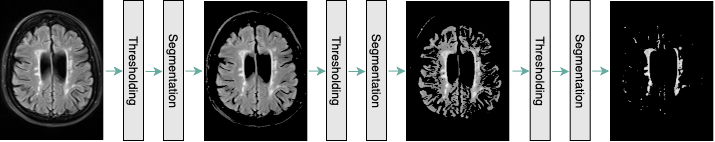

As it is mentioned earlier, the classification task is mainly based on a specific type of white matter lesions. Hence, the CNN model, which can successfully classify patients based on the aforementioned biomarker, should mostly attend to the areas of the input image containing white matter lesions. Consequently, we designed a component for white matter lesion segmentation to be performed on the given MR images. This component is comprised of three steps:

For each step, we perform adaptive thresholding based on the Otsu’s threshold selection method [23]. In each stage, the objective is to find the value of pixel intensity at which the between-class variance is maximized. This threshold value, , divides the input image pixels into two groups and :

This process is conducted during each step, and the former output image is passed as the input image of the latter (Fig. 2). It is notable that since this method is performed on each image separately, it can adapt to images with different grayscale distributions. This enables us to segment white matter lesions in all patients regardless of the patient positioning and the device setting.